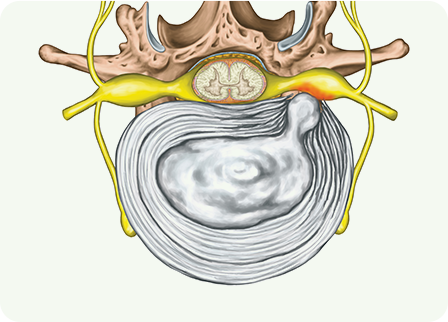

목디스크(추간판 탈출증)는 척추 사이에서 완충 역할을 하는

디스크가 손상되어 돌출하거나 신경을 압박하는 상태

입니다.

디스크는 퇴행성 변화, 과도한 압력, 잘못된 자세, 외상 등으로 인해

약화되고 섬유륜에 균열이 생겨 수핵이 탈출할 수 있습니다.